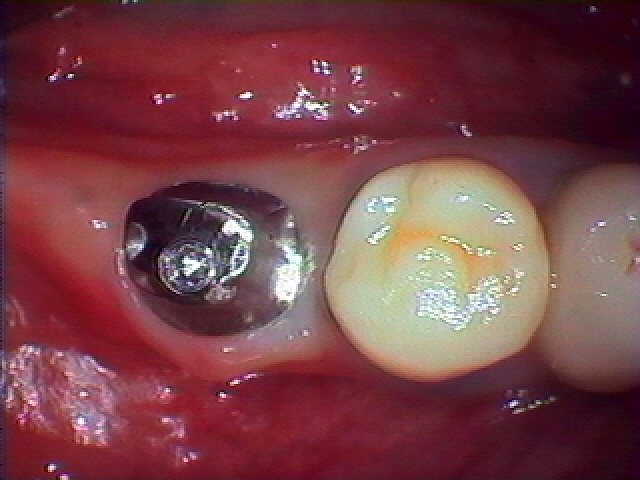

右下6番、抜歯後2ヶ月、インプラント治療|お知らせ |広島市安佐南区の歯科医院 右下6番、抜歯後2ヶ月、インプラント治療 トップ お知らせ・ブログ お知らせ 右下6番、抜歯後2ヶ月、インプラント治療 右下6番、抜歯後2ヶ月、インプラント治療 埋入前です まだへこみがありようやく傷口が塞いだ状態 歯肉を最小限めくりインプラント埋入 2ヶ月後の状態です シリコン印象後チタンにてアバットメント作成 セラミックにて綺麗に入ったところになります 咬合はこんな感じです Web診療予約 初めての方へ 選ばれ続ける理由 院内設備について 歯が痛いしみる一般歯科 歯がぐらぐらする歯周病 健康な歯を保ちたい予防歯科 子供の虫歯予防をしたい小児歯科 銀歯をセラミックに審美歯科 白い歯を目指しませんか?ホワイトニング 矯正専門医がいるので安心矯正歯科 抜けた歯を補いたいインプラント・入れ歯 医院案内 スタッフ紹介 メリィハウス歯科クリニックオフィシャルホームページ ラベンダー歯科クリニックオフィシャルホームページ お知らせ・ブログ ホーム 診療科目 一般歯科 歯周病治療 予防治療 小児歯科 審美治療 ホワイトニング 矯正歯科 入れ歯・インプラント マウスピース矯正 初めての方へ 院長・スタッフ 設備紹介 医院案内・アクセス メニューを閉じる